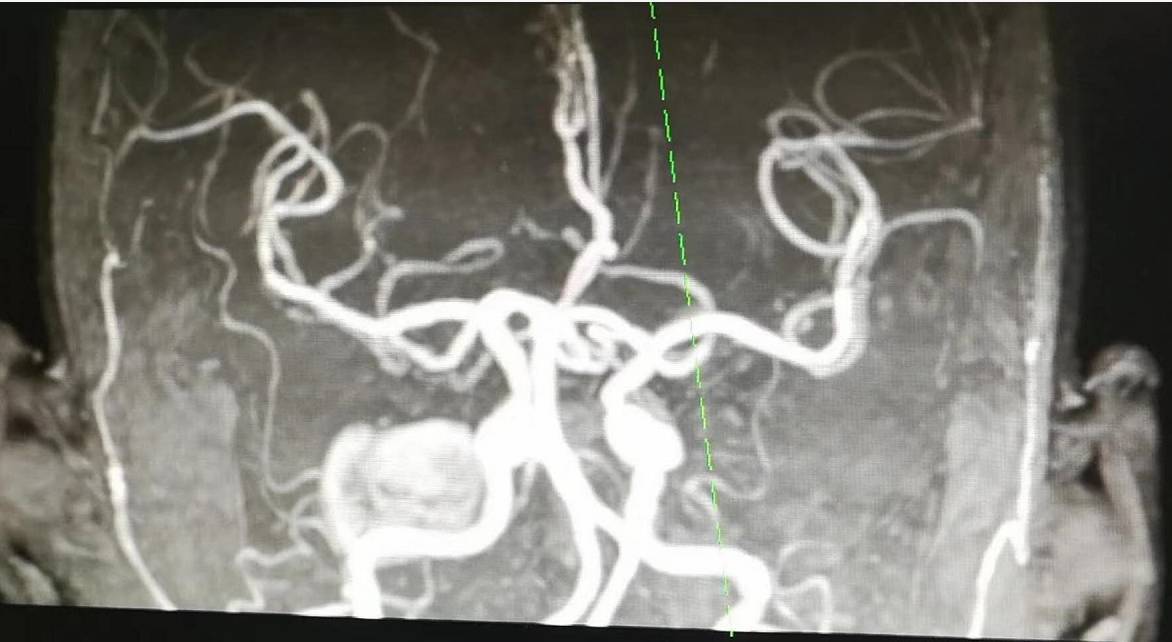

(2)心血管造影,以及X线检查等

可以通过导管和血管造影来鉴别周围血管疾病和心脏病。X线检查,胸部检查,观察是否有肿块压迫周围的大血管。脊椎血管造影术是用来了解是否存在脊椎腔等病变。